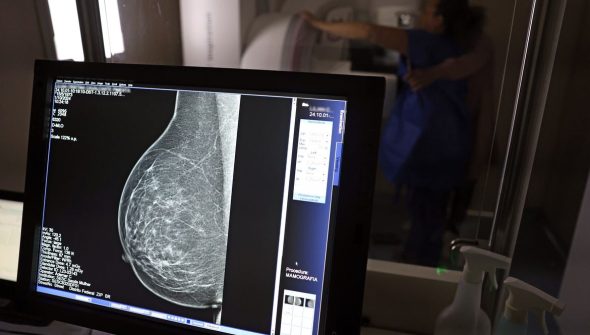

Falta de acesso a mamógrafos limita prevenção do câncer de mama

No mês de conscientização sobre o câncer de mama, um relatório destaca a importância de acesso igualitário ao rastreamento e tratamento da doença. Segundo o Atlas da Radiologia no Brasil, do Colégio Brasileiro de Radiologia e Diagnóstico por Imagem (CBR), o acesso aos mamógrafos ainda é um desafio.

O país tem 6.826 equipamentos registrados, sendo 96% em funcionamento. Metade deles está disponível no Sistema Único de Saúde (SUS), responsável por atender 75% da população. Isso equivale a 2,13 mamógrafos por 100 mil habitantes dependentes do SUS.

Na saúde suplementar, que cobre 25% da população, o cenário é mais favorável: 6,54 aparelhos por 100 mil beneficiárias, quase o triplo da rede pública. O Acre exemplifica essa disparidade — são 35,38 mamógrafos por 100 mil habitantes na rede privada, contra 0,84 no SUS.

O Brasil tem uma cobertura muito baixa de mamografias: 24%. O ideal recomendado pela Organização Mundial da Saúde é de 70%. Mesmo em lugares como o estado de São Paulo, que tem a maior concentração de mamógrafos do país, a taxa gira em torno de 26%.

Em setembro, o Ministério da Saúde ampliou as diretrizes de rastreamento, recomendando que mulheres entre 40 e 49 anos realizem mamografias, mesmo sem sintomas. De acordo com o Instituto Nacional do Câncer (Imca), mais de 73 mil mulheres recebem o diagnóstico de câncer de mama anualmente no Brasil.

“O que é efetivo na redução da mortalidade é você descobrir o tumor antes de ter sintoma clínico. Quanto menor o tumor, melhor para a gente descobrir o tratamento e maior a chance de cura. E a gente só consegue fazer isso com exames de imagem”, diz Ivie.

Ela explica que no caso de diagnóstico de um câncer de mama com menos de 1 cm, a chance de cura é de 95% em cinco anos, independentemente se ele é do tipo mais agressivo. “E esses tumores só vão ser detectados na mamografia. Essas pessoas que têm que ir fazer mamografia são mulheres saudáveis. Não são mulheres doentes”, acrescenta.